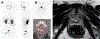

Purpose: Prostate-specific membrane antigen (PSMA)-targeting PET radiotracers reveal physiologic uptake in the urinary system, potentially misrepresenting activity in the prostatic urethra as an intraprostatic lesion. This study examined the correlation between midline 18 F-DCFPyL activity in the prostate and hyperintensity on T2-weighted (T2W) MRI as an indication of retained urine in the prostatic urethra.

Results: Midline activity on PSMA PET imaging was seen in 14 patients included in the case group, whereas the remaining 71 with no midline activity constituted the control group. A total of 71.4% (10/14) and 29.6% (21/71) of patients in the case and control groups had urethral hyperintensity on T2W MRI, respectively ( P < 0.01). Patients in the case group had significantly larger mean urethral dimensions, larger prostate volumes, and higher incidence of severe urethral curvature compared with the controls.

Conclusions: Stagnated urine within the prostatic urethra is a potential confounding factor on PSMA PET scans. Integrating PET imaging with T2W MRI can mitigate false-positive calls, especially as PSMA PET/CT continues to gain traction in diagnosing localized prostate cancer.